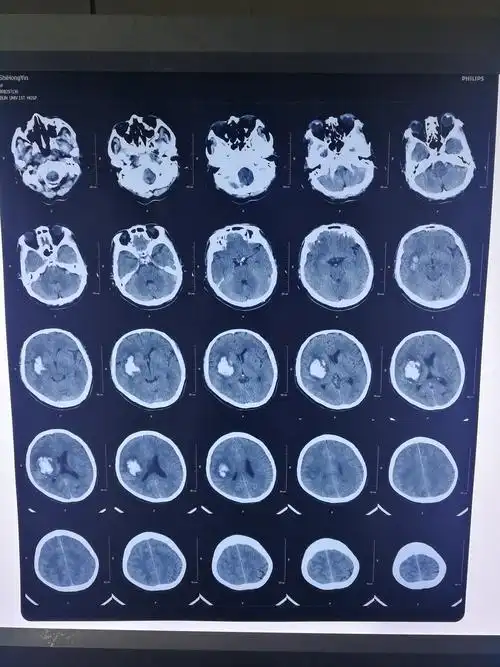

患者:施洪印,男,68岁,右侧基底节区脑出血